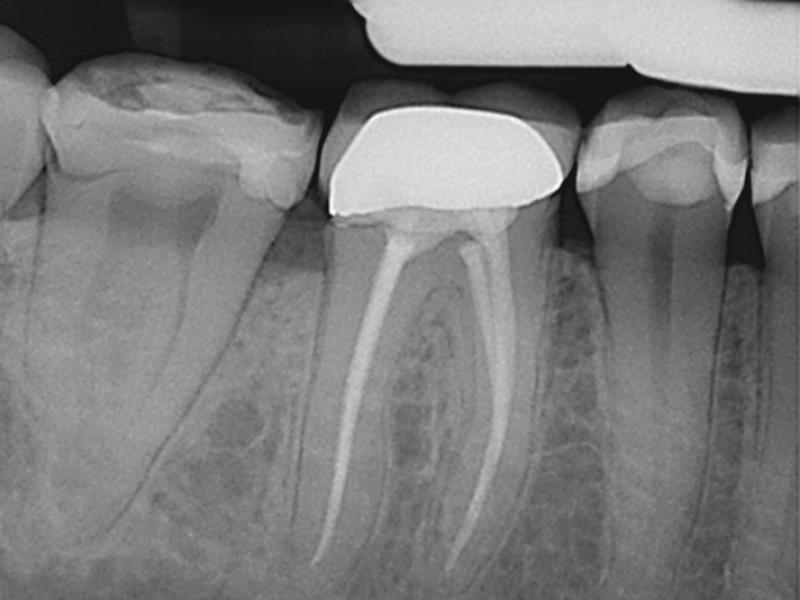

Post-Op